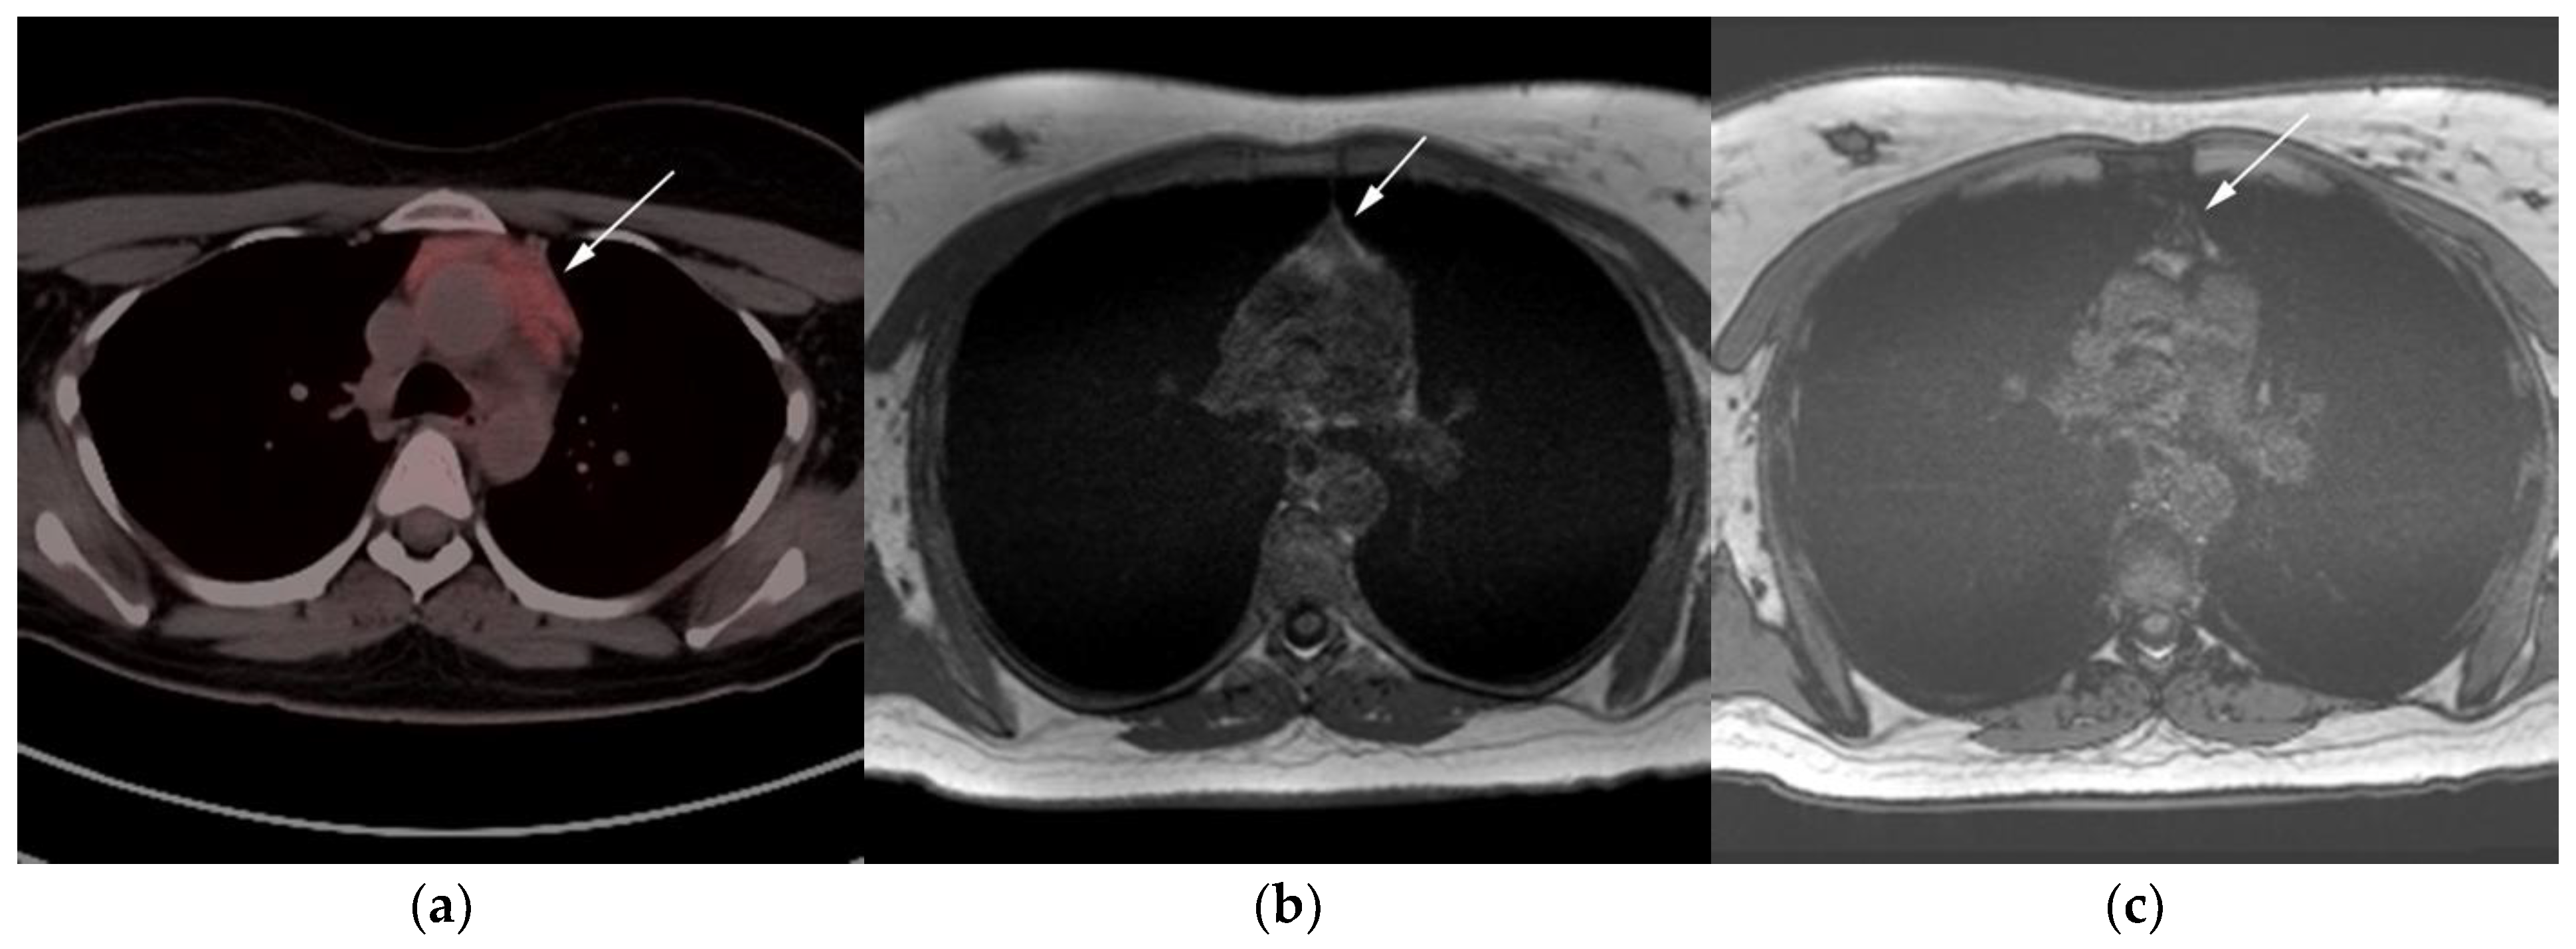

Figure 7.

Imaging in a 20-year-old female with history of classic Hodgkin’s lymphoma (CHL) who had 4 cycles of chemotherapy. (a) Axial 18F-FDG PET/CT showing residual wedge-shaped/triangular activity seen within the anterior mediastinum (arrow). There was concern for residual disease vs. thymic rebound hyperplasia. (b) MRI axial T1 in phase and (c) MRI axial T1 out of phase show intermedial signal on T1 in phase (arrow) with dropped signal on the out of phase sequence (arrow), consistent with fat content due to thymic rebound hyperplasia.

Figure 8.

Imaging in a 60-year-old female presenting with ill-defined anterior mediastinal mass. (a) Axial 18F-FDG PET/CT showing ill-defined hypermetabolic mass within the anterior mediastinum (arrow). This was biopsy-proven thymic carcinoma. (b) MRI T1 in phase sequence, (c) MRI T1 out of phase—note there is no dropped signal on the T1 out of phase (arrows) due to lack of fat. This is consistent with residual disease.